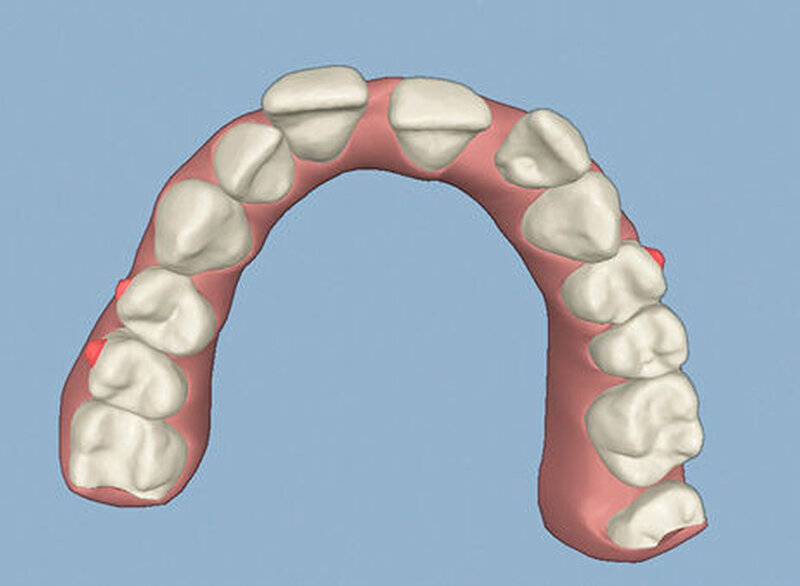

Die Sulkustiefen konnten auf etwas weniger als 4 mm reduziert werden, während der Blutungs- und Plaque-Index bei weniger als 15 Prozent lag. Daher wurde eine kieferorthopädische Behandlung über die nächsten zwei Jahre in Kombination mit engen zahnärztlichen Kontrollen geplant. Als Mittel der Wahl entschieden wir uns gemeinsam mit dem Patienten für das Invisalign-System, da hiermit sowohl eine Schienung als auch eine kraft-arme Bewegung der Zähne möglich sein sollte. Für den Frontzahnbereich wurden keine Attachments geplant, so dass hier eine unnötige Hebelwirkung umgangen werden konnte (Abbildung 3).

Um einen kompletten Lückenschluss im Oberkiefer zu ermöglichen, musste im Unterkieferfrontzahnbereich zusätzlich zur Derotation und Positionierung der Zähne – insbesondere Zahn 41 – von approximaler Schmelzreduktion, kurz ASR , Gebrauch gemacht werden, um einer Tonn`schen Diskrepanz entgegenzuwirken (siehe dazu Abbildung 7 auf Seite xy).